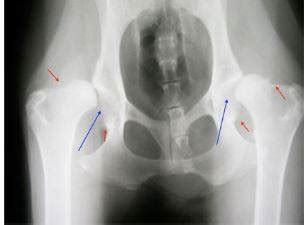

Hoci ide o robustné plemeno, šľachtenie si vybralo svoju daň a nemeckí ovčiaci sú náchylní na niektoré dedičné ochorenia. Medzi najčastejšie patria dysplázia bedrového a lakťového kĺbu (DBK a DLK). Ďalej sa môžu stretávať s degeneratívnou myelopatiou (ochorenie miechy) alebo spondylózou (stuhnutie chrbtice). Okrem toho sa u nemeckých ovčiakov vyskytuje viac očných ochorení a alergií.

Ovčiaci, podobne ako mnoho iných veľkých plemien, sú náchylní k problémom s kĺbami. Je dôležité zabrániť tomu, aby príliš rýchlo vyrástli. Ako ukazujú štúdie, ochorenie dysplázia bedrového kĺbu nie je spojená len s genetickou predispozíciou, ale tiež sa štýlom kŕmenia. Strava s príliš vysokou energetickou hodnotou a s veľkým obsahom tuku urýchľuje už aj tak rýchly rast šteňat a môže dokonca v starobe spôsobiť problémy s kĺbami. Preto si nechajte od chovateľa poskytnúť presné odporúčanie na kŕmenie a venujte pozornosť vhodnej výžive šteňaťa. Chovateľ vám tiež poradí, aby ste nepreťažovali šteňa tréningom. Najprv by ste sa mali úplne vyhnúť chôdzi po schodoch. Odpočinok podporuje zdravý vývoj kostí a kĺbov.